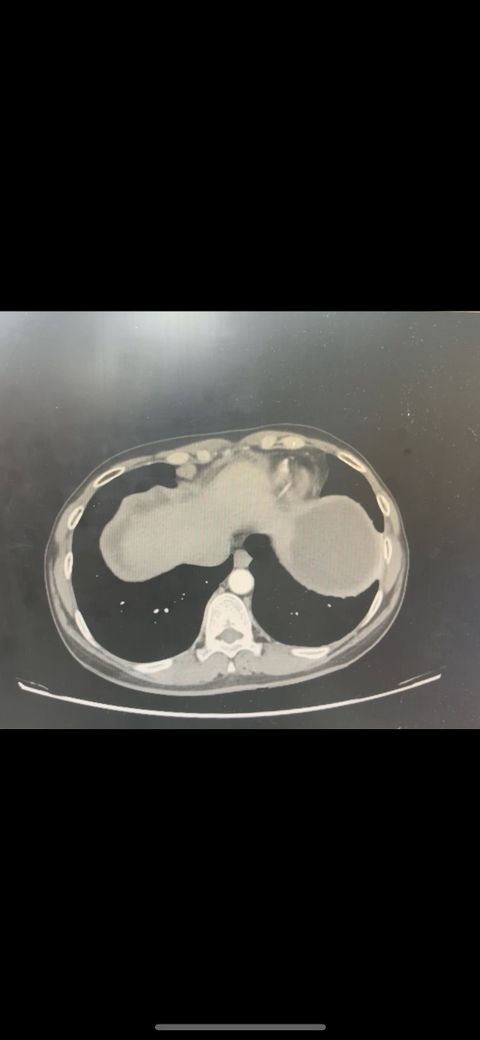

복부 ct 판독 부탁드립니다 (contrast)

결과는 3일 뒤 보긴 하는데 우선 영상만 있는 상태라 영상 캡쳐 한 거 대략적으로라도 확인해주실 수 있나요.. !!!!!!!!!!

• 2번 째 사진

*** 먼저 답변드리기에 앞서 상기 질문에 대한 답변은 굉장히 제한된 답변이고, 경우에 따라 틀린 답변이 될 수 있습니다. CT의 경우 단면을 연속적으로 봐야 의학적인 설명이 가능하기 때문에 일부 사진만으로는 해석이 어려울 수 있습니다.

위 사진에서는 비장비대의 가능성과 자궁쪽으로 혹이 일부 보이는 소견이 의심되나, 정확한 판독은 3일 뒤에 받아보시는 것이 도움이 될 수 있겠습니다.